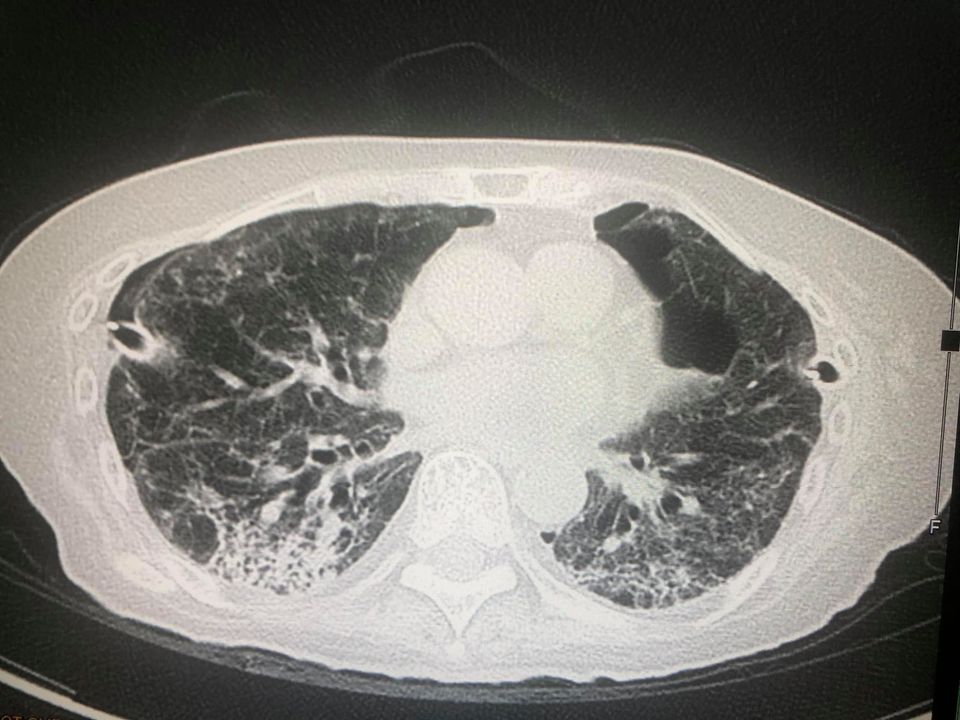

ล่าสุดพบผู้ป่วยไทยปอดรั่วเองทั้ง 2 ข้าง เป็นผลจากการที่เนื้อปอดถูกทำลายโดยเชื้อไวรัสโควิด-19 โดยเป็นผู้ป่วยหญิงไทยอายุ 77 ปี ไม่สูบบุหรี่ ปกติแข็งแรง ไม่มีปัญหาทางปอด ยังไม่ได้ฉีดวัคซีนป้องกันโรคโควิด

- วันที่ 2 กันยายน ทำคอมพิวเตอร์สแกนปอดพบพังผืดทั่วปอดร่วมกับหลอดลมเล็กๆโป่งพอง

- วันที่ 10 กันยายน ได้ทำการผ่าตัดปอดข้างขวาเพราะปอดขวาไม่ขยายตัวเต็มที่ ด้วยการส่องกล้องเข้าไปในช่องทรวงอกข้างขวา พบถุงลมพองโตที่ผิวของยอดปอดข้างขวาด้านบนและด้านล่าง ต้องตัดปอดเฉพาะส่วนนั้นและเย็บปิด ตัดเยื่อหุ้มปอดด้านขวา ใส่แป้งทัลค์ เข้าช่องปอดขวา และผ่านท่อระบายลมข้างซ้าย เพื่อให้เยื่อหุ้มปอดข้างขวาและซ้ายติดกัน

และส่งชิ้นเนื้อปอดตรวจทางพยาธิวิทยา พบว่า เนื้อปอดถูกทำลาย มีทั้งอักเสบและพังผืดทั่วไป มีถุงลมพองในเนื้อปอด ขณะนี้ยังต้องใส่ท่อระบายลมทั้งสองข้าง